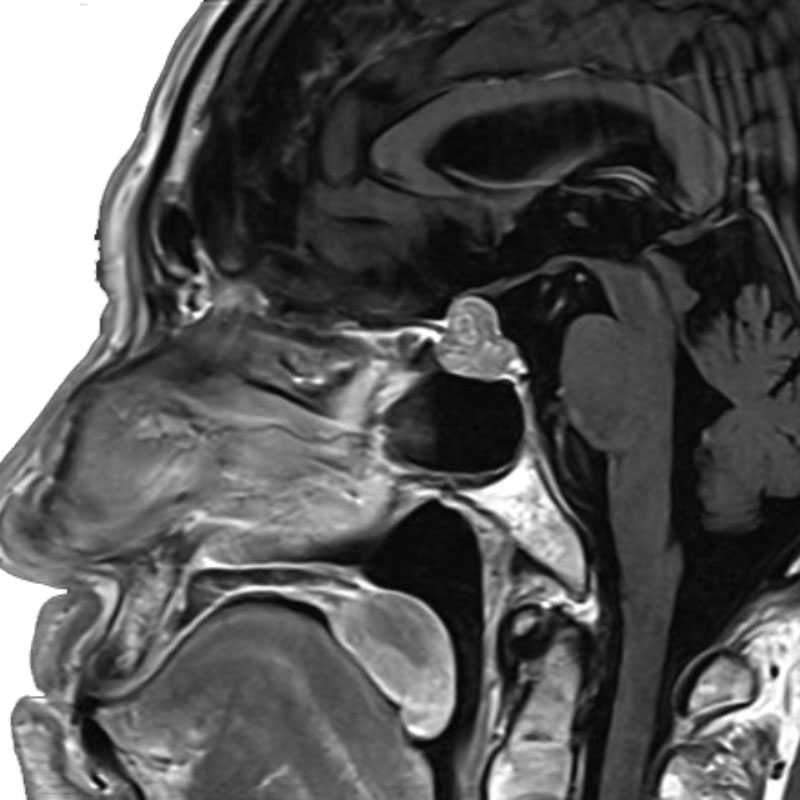

5月15日(金)

右顔面痙攣

微小血管減圧術

岩井/古部

脳動脈瘤(Acom)

クリッピング術

松田/濵田/元永